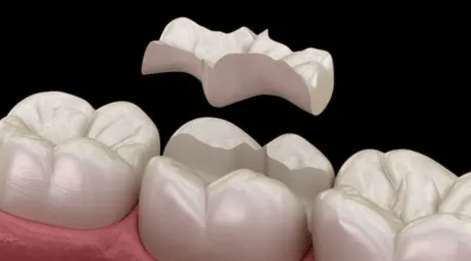

修复治疗

嵌体/全冠:牙体缺损较大、颌面及邻接面形态无法用充填法恢复时,可采用嵌体或者全冠来修复。